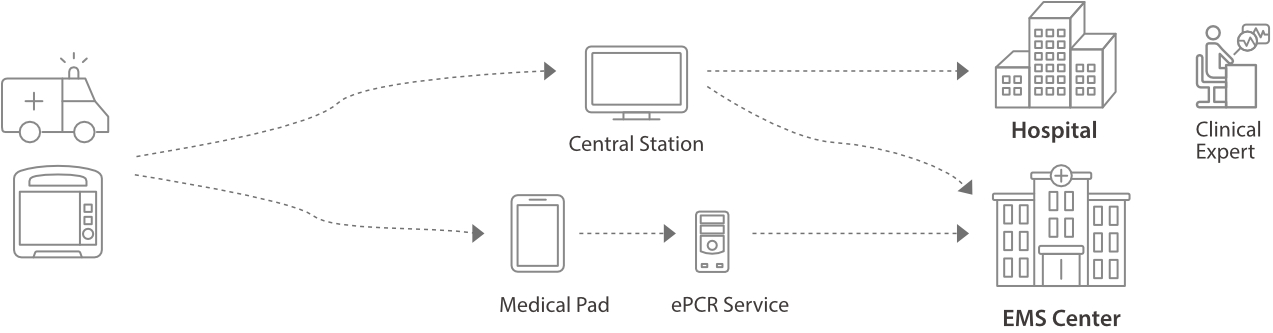

Kurtarma ??geni, Daha Kapsaml?

- D60â?n yap?land?r?lm?? bilgilendirme protokolleri, sonraki resÞsitasyon olaylar?nda resÞsitasyon ekiplerinin performans?n? art?r?r.

- D60'daki e?itim modu, ger?ek operasyon deneyimi elde etmenize yard?mc? olur.

Daha H?zl? ResÞsitasyon

Yap?land?r?lm?? Bilgilendirme

- D60â?n yap?land?r?lm?? bilgilendirme protokolleri, sonraki resÞsitasyon olaylar?nda resÞsitasyon ekiplerinin performans?n? art?r?r.

Uygulamal? E?itim

- D60'daki e?itim modu, ger?ek operasyon deneyimi elde etmenize yard?mc? olur.

Yap?land?rma profilleri, farkl? klinik senaryolar veya varsay?lan de?erler, ekran dÞzeni ve sistem yap?land?rmas? gibi kullan?m gereksinimleri i?in kolayca ?zelle?tirilebilir ve yÞklenebilir.